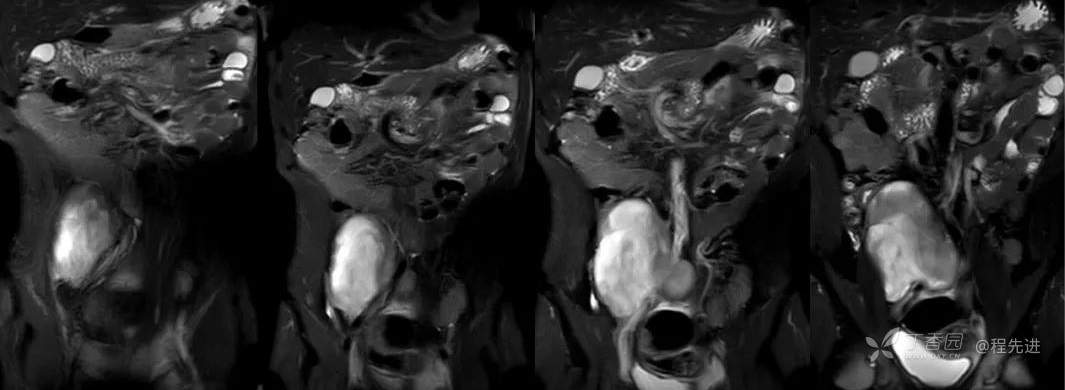

MR

从左到右依次是T1、T2、DWI、ADC

冠状位T2